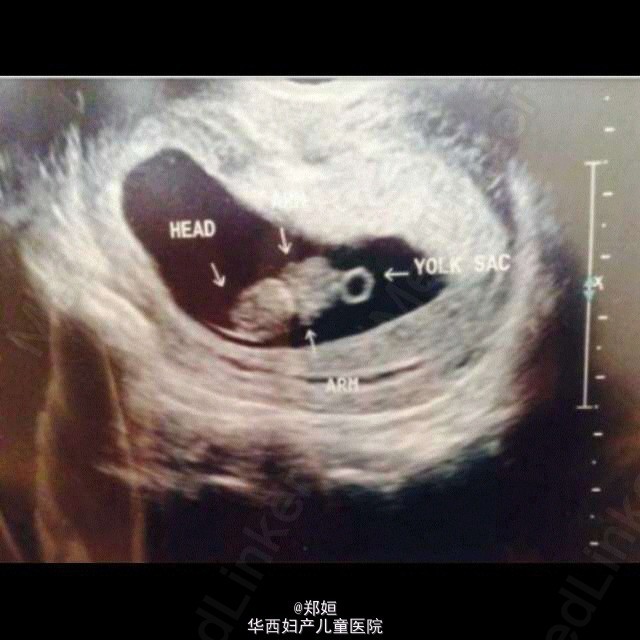

孕早期B超示胎儿图像

最近看到的一个病例,跟大家分享